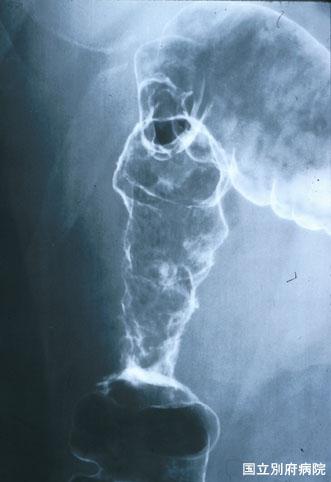

症例提示(所在地,施設名等): 大分県・ 別府医療センター

疾患(病理主体)の分類炎症性・潰瘍性疾患/虚血性腸炎

部位(臓器別)大腸/上行

検査方法X-P

病変の最大径(ミリ)40以上